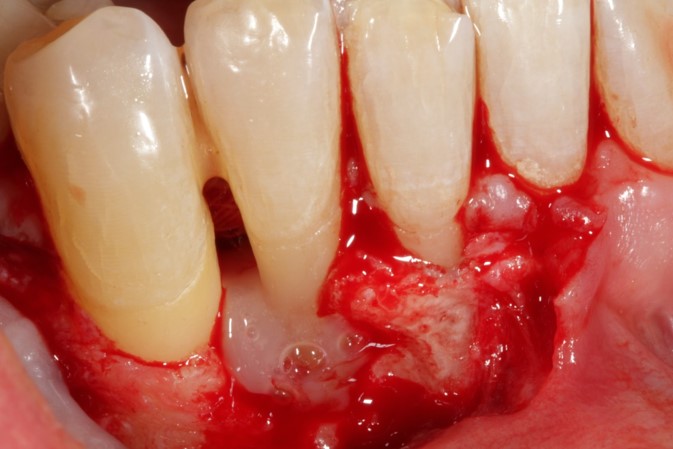

04/08 - Intra-operative view of the defect area.

Non-contained intrabony defect treated using Straumann® Emdogain® and a synthetic bone grafting material - Prof. Dr. Dr. A. Kasaj